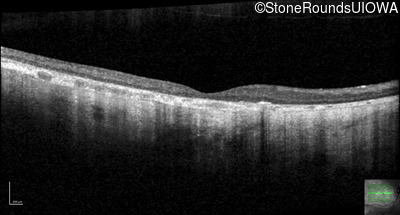

Optical Coherence Tomography - Right - 10/200 sc

Exemplar / OCT Stack

OCT Stack